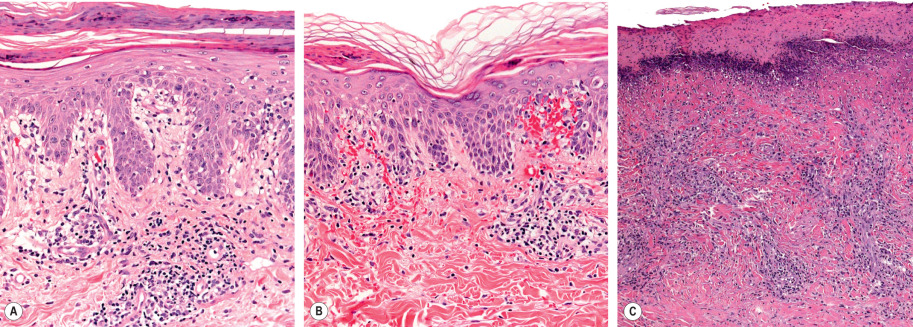

Pityriasis lichenoides exhibits a superficial perivascular interface dermatitis in all cases ( Fig. 9.5 ). Those lesions at the acute end of the spectrum contain a denser infiltrate that may be top-heavy and wedge-shaped. Lymphocytes predominate in the infiltrate, although neutrophils may be admixed. The epidermis shows focal parakeratosis and evidence of damage ranging from edema to extensive epidermal necrosis in well-developed lesions. Extravasation of erythrocytes is a frequent finding. The typical histopathologic alterations accompany the presence of crusts, vesiculopustules, and ulcers. Lymphocytic vasculitis is sometimes described, but true fibrinoid necrosis of blood vessels is not seen (and use of this histologic term can be confusing to nondermatologists). All of these changes are blunted in the more chronic skin lesions, where the principal microscopic features include parakeratosis and a milder interface lymphocytic infiltrate that is accompanied by focal keratinocyte necrosis and mild erythrocyte extravasation. Lymphoid atypia is not a standard feature of pityriasis lichenoides. Although some pathologists allow occasional atypical lymphocytes, others regard this as a sign of lymphomatoid papulosis or another form of CTCL.